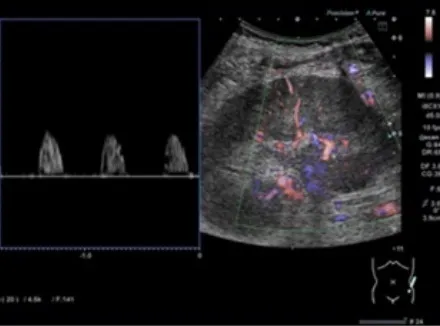

A tomografia computadorizada de abdome revelou um rim direito aumentado, com a presença de um cálculo coraliforme na junção ureteropélvica, atrofia cortical e dilatação do cálice, uma aparência referida como o "sinal da pata de urso."

Foi iniciado tratamento com antibióticos intravenosos e realizada uma nefrostomia percutânea. A cultura da drenagem identificou o crescimento de Proteus mirabilis. Após avaliação com cintilografia, foi identificada a ausência de função renal no rim direito, levando à realização de uma nefrectomia.

Foi feito o diagnóstico de pielonefrite xantogranulomatosa.

A pielonefrite xantogranulomatosa, uma forma de pielonefrite crônica, está tipicamente associada à obstrução por cálculos e infecções recorrentes do trato urinário. As complicações podem incluir abscessos e fístulas. A perda da função renal é comum, e a nefrectomia é o tratamento definitivo. O paciente recebeu alta 5 dias após a cirurgia e apresentava-se bem, com função renal estável, após 1 mês de acompanhamento.